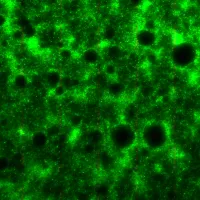

Image galleries

Explore the high-quality images and videos we produce.

Southampton Imaging

Imaging has become an essential part of scientific research, from biomedical sciences to engineering to optoelectronics.